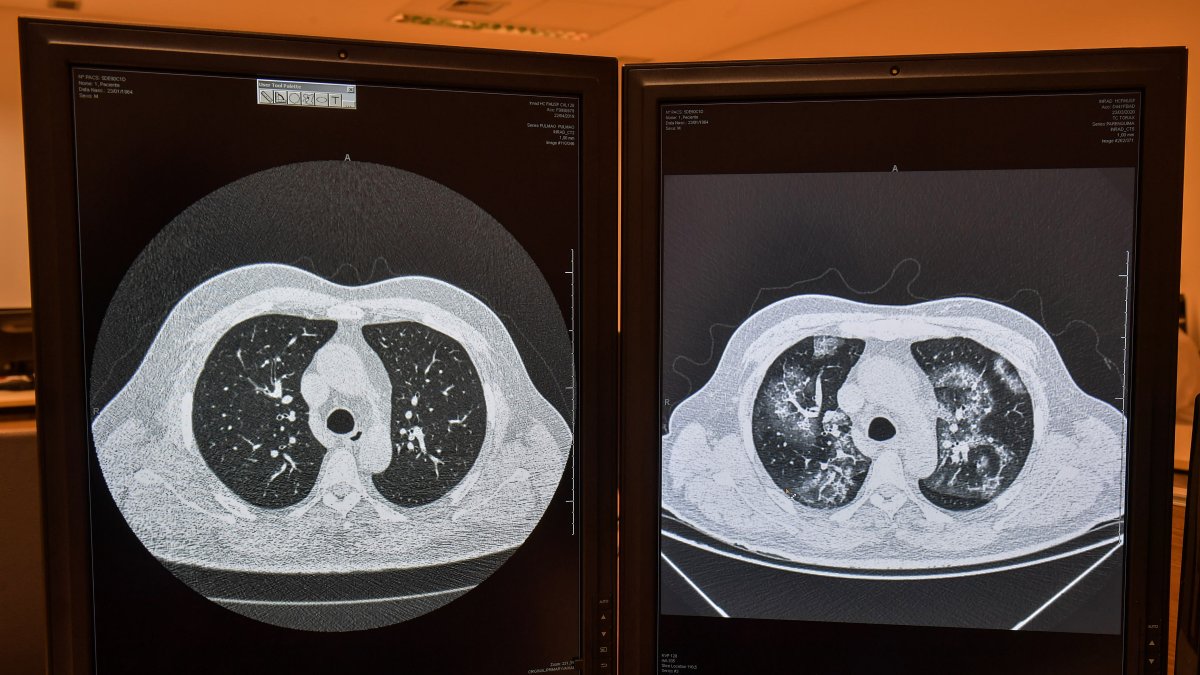

Imágenes de tomografías comparando un pulmón sano (izq) con uno afectado por coronavirus en el mismo paciente.

"Es el aspecto más típico de la neumonía por covid. El software marca esas áreas, dice cuál es la probabilidad de tener covid e indica el porcentaje de pulmón que está enfermo", explica Marcio Sawamura, vicedirector del Instituto de Radiología del Hospital de las Clínicas de la Facultad de Medicina de la Universidad de Sao Paulo (USP).